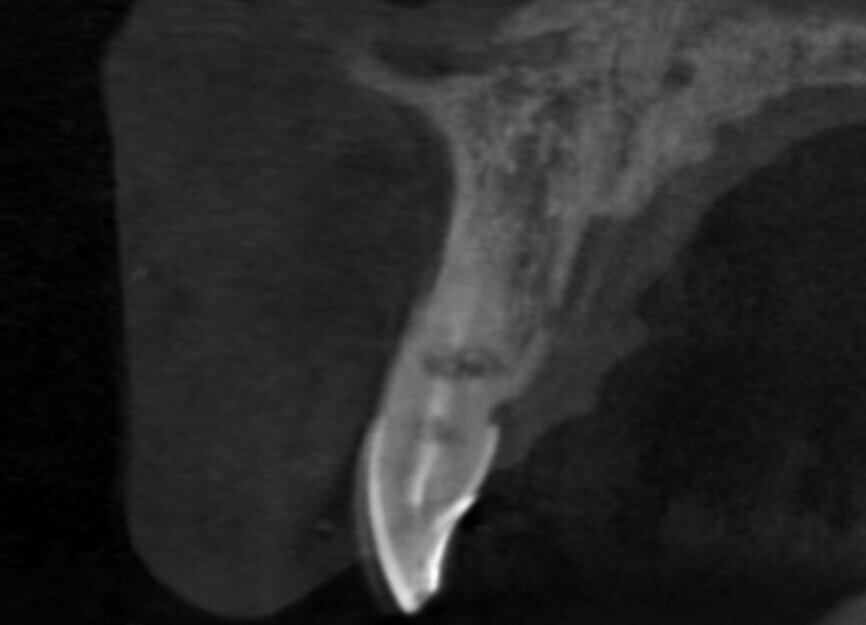

A 52-year-old man, a non-smoker in good general health, was referred after diagnosis of post-traumatic resorption affecting the roots of teeth #11 and #12 (Figs. 1a & 1b). The patient had previously consulted with an endodontist, who stated that both teeth were hopeless and therefore extractions were required. Clinical examination revealed a complete, healthy periodontium around tooth #12 with no sign of infection. At tooth #11, a slight tissue oedema associated with chronic irritation in front of the extensive resorption was observed. The intermaxillary relationship was normal, and the analysis of the smile showed a low smile line (Fig.2). Tooth #21 had been replaced by an implant-supported crown. The previously requested CBCT scan showed that the resorption process was more advanced at tooth #11 (Fig. 3).

We used the previous CBCT scan to evaluate the bone volume in the apical area of teeth #11 and #12, as well as the integrity of the buccal plate at both sites (Fig.4). The examination of the CBCT scan showed that the buccal plate was intact 3 mm below the gingival level and this correlated to the findings of the clinical examination. The future extraction sockets were determined as Class I according to Elian et al.[2]

Fig 3

Fig 4